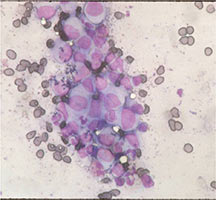

Microscopic Pathology

- Langerhans cell is diagnostic and clonal proliferation

- Nuclei show prominent nuclear groove (coffee-bean)

- Also composed of eosinophils and other inflammatory cells (non diagnostic component)

- Ratio of inflammatory cells to Langerhans cells varies

- Mitotic activity low

- Eosinophils dominate some areas forming diffuse sheets, excluding Langerhans cells

- Birbeck Granules: Electron Microscopy demonstrates granules that often take the form of a tennis raquet and form from complex invaginations of the cell membrane

- Vimentin, CD1 and S-100 positivity